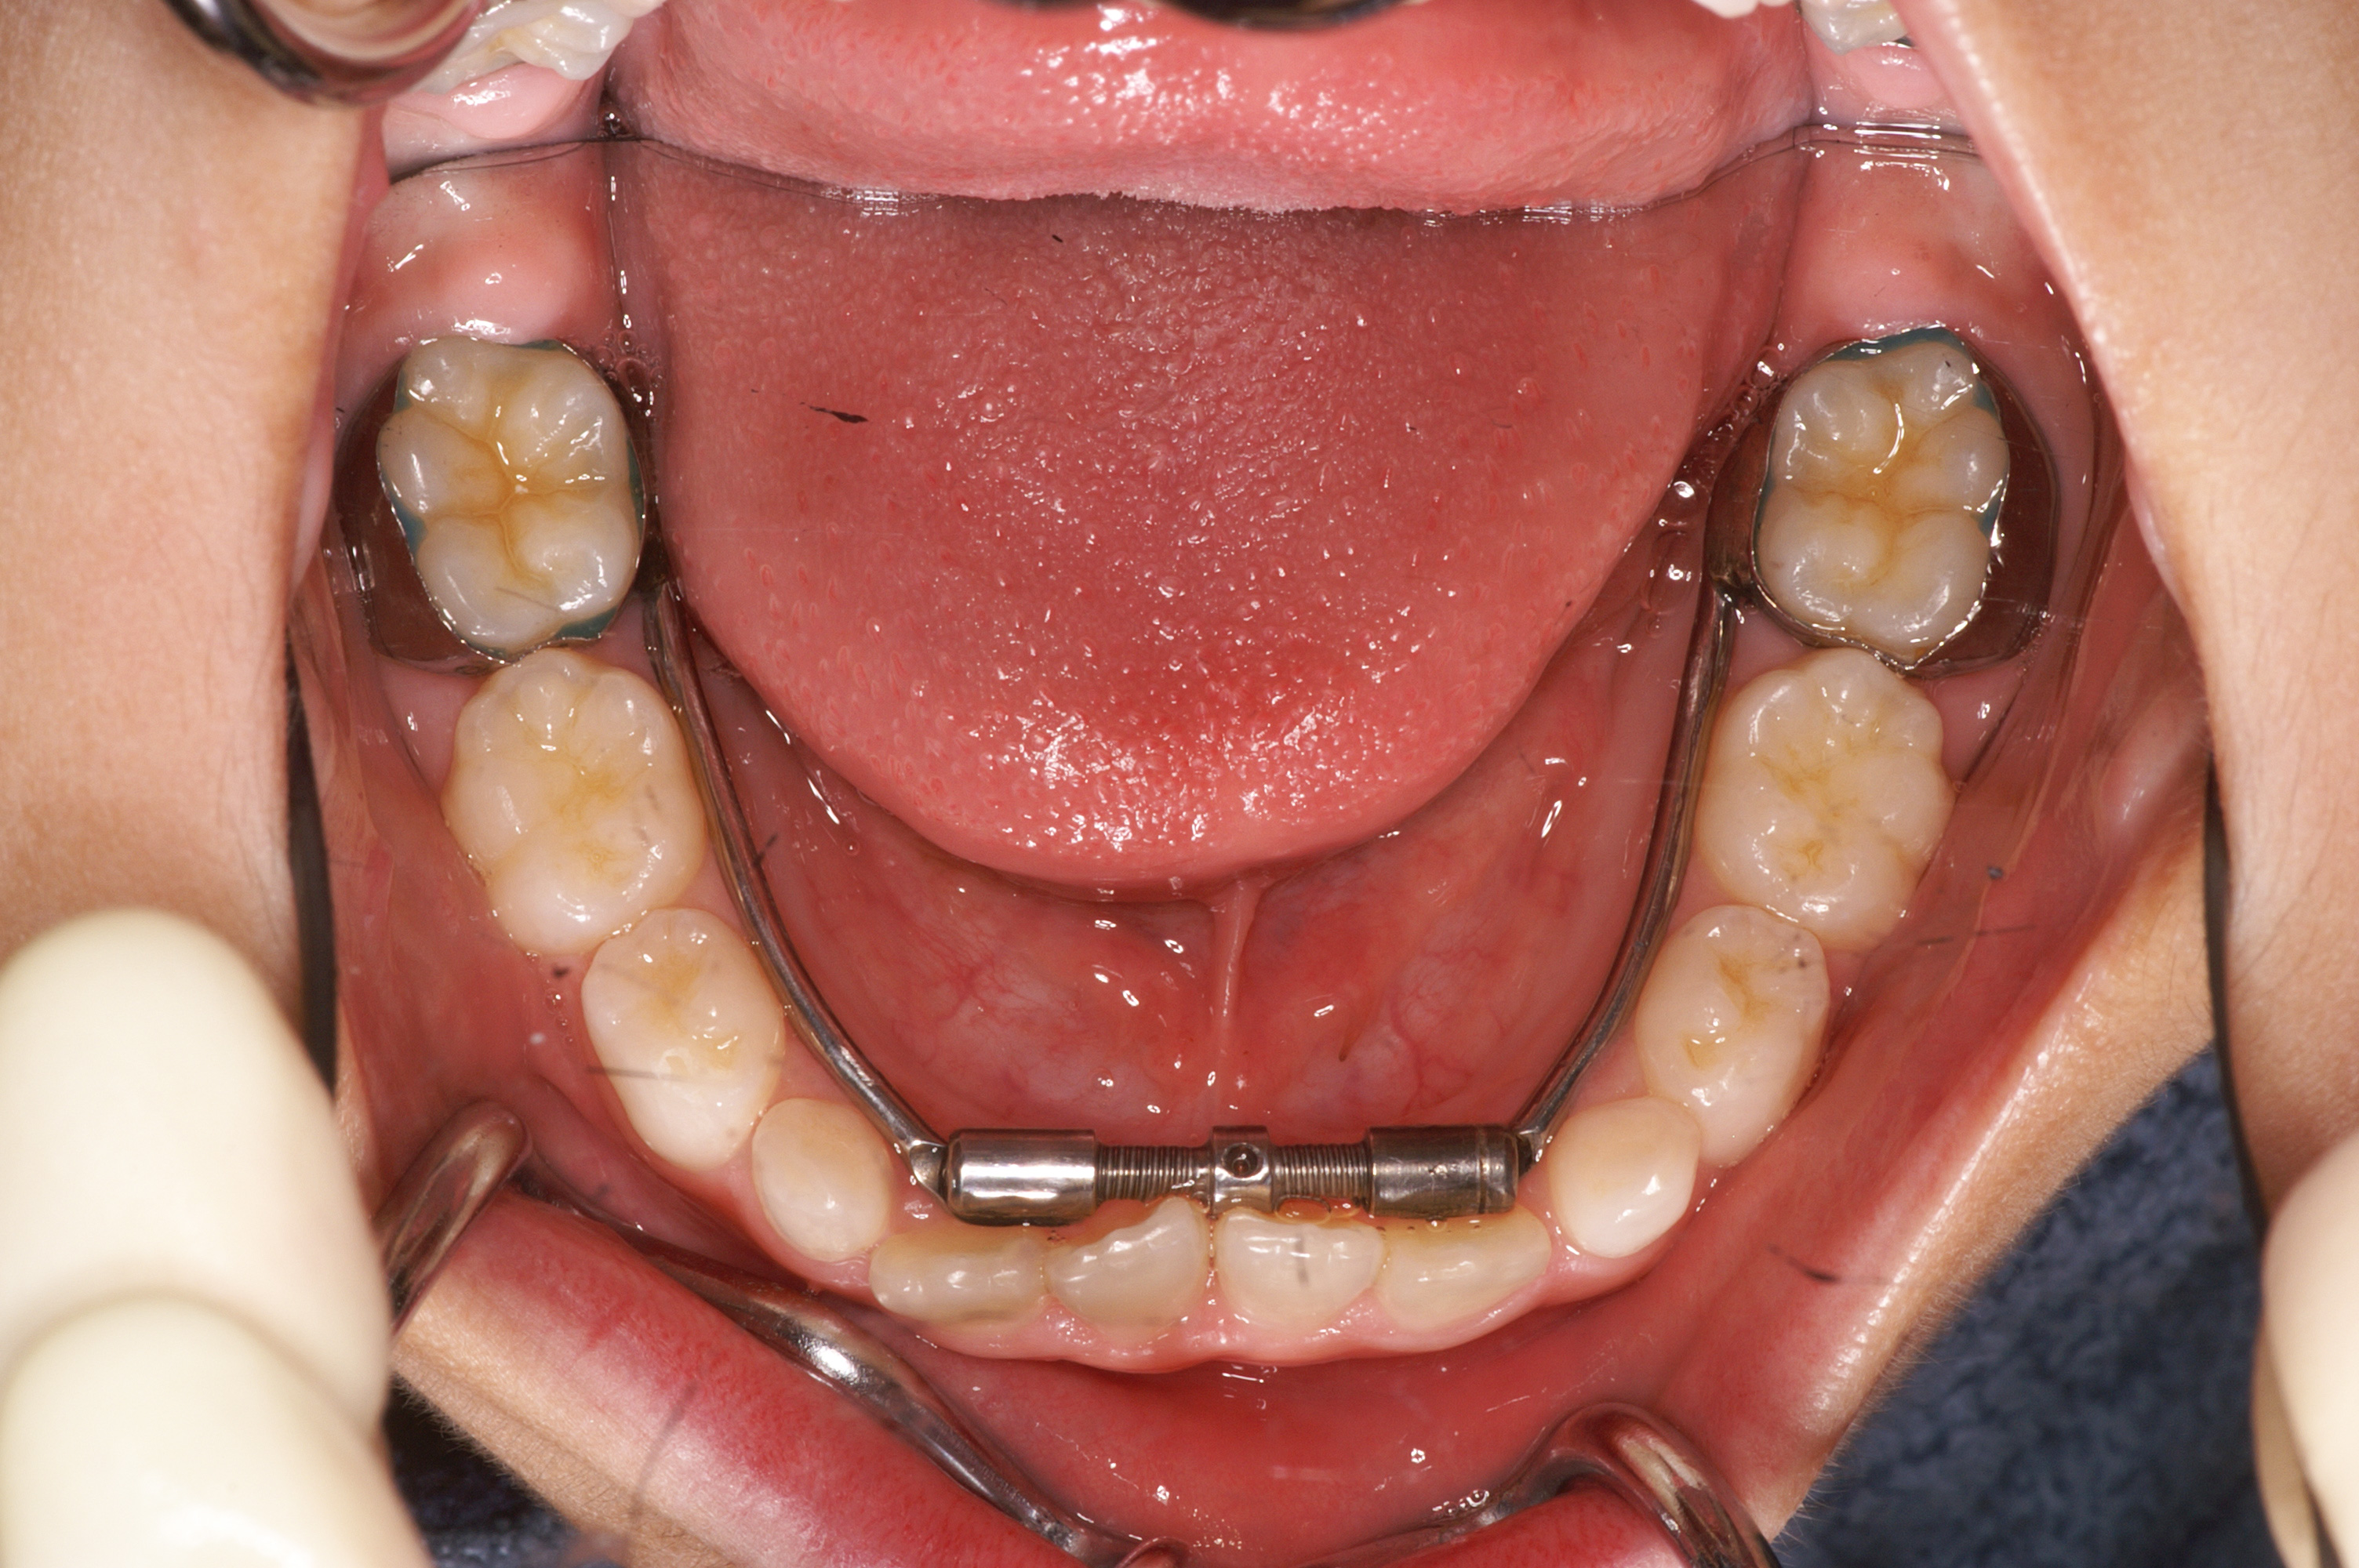

当院では、口呼吸が原因となる不正咬合の矯正に特化し、スケルトンタイプの固定式拡大装置を採用しています。この装置は、上顎の拡大に効果的で、鼻腔を広げることで鼻呼吸を促し、口呼吸の改善に繋がります。また、固定式の装置の中でも痛みが少なく、顎が広がることで歯が並ぶスペースが増え、後の矯正治療にも有利に働きます。